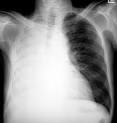

Atelectasis is defined as diminished volume affecting all or part of a lung. Note that the term atelectasis is typically used when there is partial. It may include a lung subsegment or the entire lung and is almost always a secondary. Collapsed Lung (Atelectasis) - Cedars-Sinai Learn more about collapsed lung (atelectasis including symptoms, prevention, causes and risk factors, diagnosis and treatment). Atelectasis - , the free encyclopedia Atelectasis is the collapse or closure of a lung resulting in reduced or absent gas exchange.

It may affect part or all of a lung. Org Lung atelectasis refers to collapse or incomplete expansion of pulmonary parenchyma. Atelectasis (at-uh-LEK-tuh-sis) is a condition in which one or more areas of your lungs collapse or don t inflate properly.

Atelectasis refers to collapse of part of the lung. Atelectasis - Mayo Clinic Atelectasis (at-uh-LEK-tuh-sis) a complete or partial collapse of a lung or lobe of a lung develops when the tiny air sacs (alveoli) within the lung become.